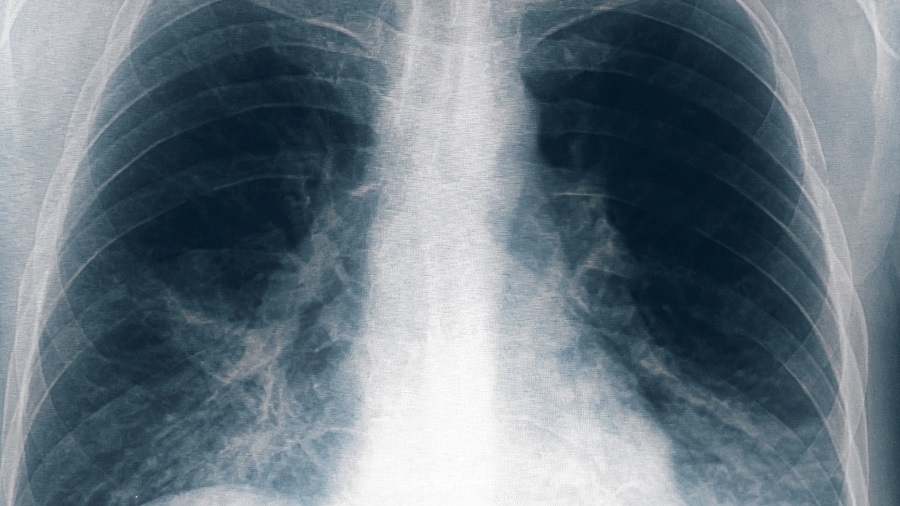

Ocho nuevos casos de neumonía bilateral en Tucumán

Otras ocho personas resultaron afectadas por el brote de neumonía bilateral causado por la bacteria legionella, una de ellas en estado grave, tras un cambio en el criterio de selección de los pacientes, con lo que suman 13 casos en total y seis fallecidos, informó el ministro de Salud de Tucumán, Luis Medina Ruiz.

"Estamos hablando de fiebre, de algún catarro respiratorio, o demás, de distinta gravedad, no necesariamente neumonía bilateral", detalló el titular de la cartera sanitaria tucumana.

"En general, esta enfermedad produce una mortalidad del 10 o 20% y es mucho mayor cuando se trata de neumonías", indicó el médico y añadió que "la mayoría de las personas que están graves o fallecieron son mayores, con comorbilidades severas."